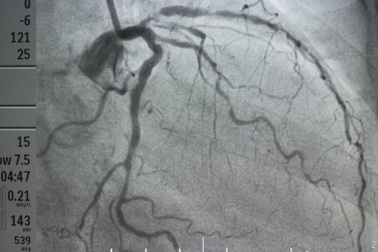

Tắc động mạch vành: Người trẻ 40 tuổi đã gục ngãPGS.TS Nguyễn Hữu Ước, Trưởng khoa Tim mạch và lồng ngực (Bệnh viện Việt Đức) cảnh báo, căn bệnh tắc động mạch vành nhiều người nhầm tưởng chỉ gặp ở người già. Hiện nay, có những bệnh nhân 40 - 50 tuổi đã bị tắc động mạch vành, có thể gây đột tử trong tích tắc.